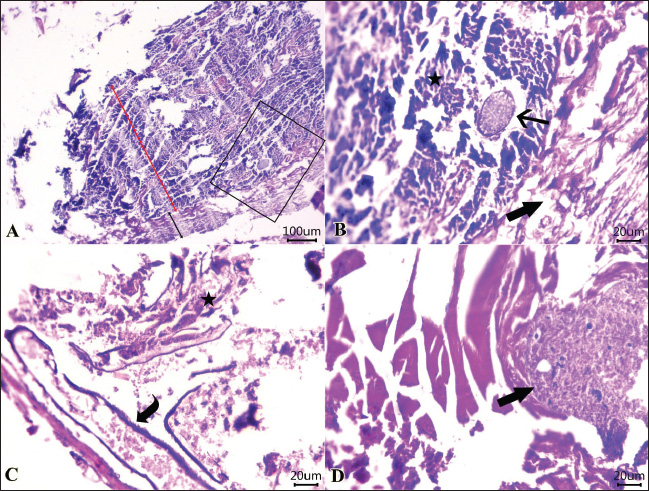

Examined sections from the intestine (Fig. 3) showed necrotic enteritis with the presence of rounded to ovoid-shaped structures “may be parasitic elements” in between necrotic and detached enterocytes. Moreover, extensive myonecrosis is observed at the muscular layer and congested vasculature. Sections from the intestine (Fig. 4) showed necrotic epithelial lining mucosa beside the vacuolated and necrotic muscular layer. “Oval-shaped protozoal element” were also embedded between the necrotic columnar mucosal epithelium. Furthermore, congestion and hemorrhages within the mucosal and submucosal layers, as well as myolysis within the musculosa, were also detected.

Fig. 4. Photomicrographs of H&E-stained sections of the intestine of shrimp showing: A, B, C, D: Protozoal element (arrow) in between necrotic columnar mucosal epithelium (star), congestion (curved arrow), hemorrhages within the mucosal and submucosal layers, and extensive myonecrosis (thick arrow) at the muscular layer. (Scale bar 100 μm, and high magnification 20μm). (“Red double-headed arrow” refers to mucosa and submucosa, while, “black double-headed arrow” refers to muscular layer).